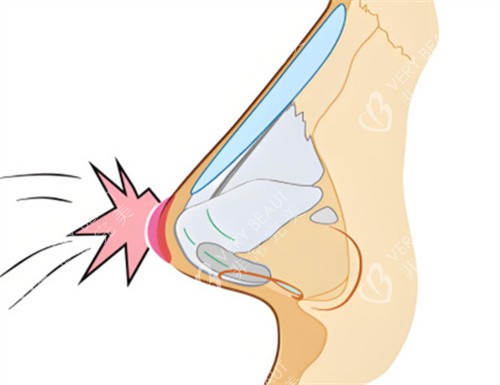

李保锴的鼻修复技术特点

他擅长采用肋软骨、鼻中隔等自体材料进行鼻部重建,重视鼻部功能与形态协调。尤其在处理鼻小柱疤痕、鼻翼后缩、鼻孔不对称等复杂问题时经验充足。

李医生强调鼻部设计的整体协调,推崇自然风格的鼻型。术后结果不仅触感柔软,还可揉捏,且长期稳定性较好,力求减少再次修复的可能。